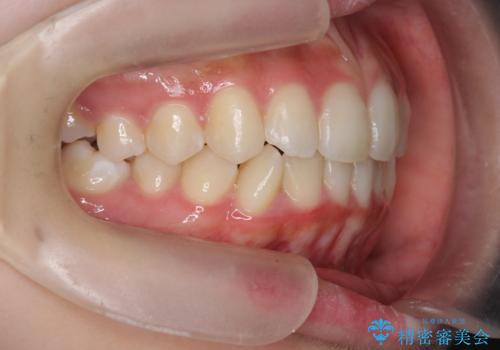

インビザラインライトで行う短期マウスピース矯正治療

- 前歯のガタつきを並べたいたいと、矯正治療を希望され来院されました。

とにかく短期間で前歯だけの治療を行いという希望が強く、全体矯正と前歯だけの部分矯正の仕上がりのイメージを確認したのち14枚のマウスピースで前歯のみの矯正治療を行っていくこととしました。

インビザラインライトは軽度なガタつきや傾斜の改善に用いられる全14枚のマウスピース矯正です。